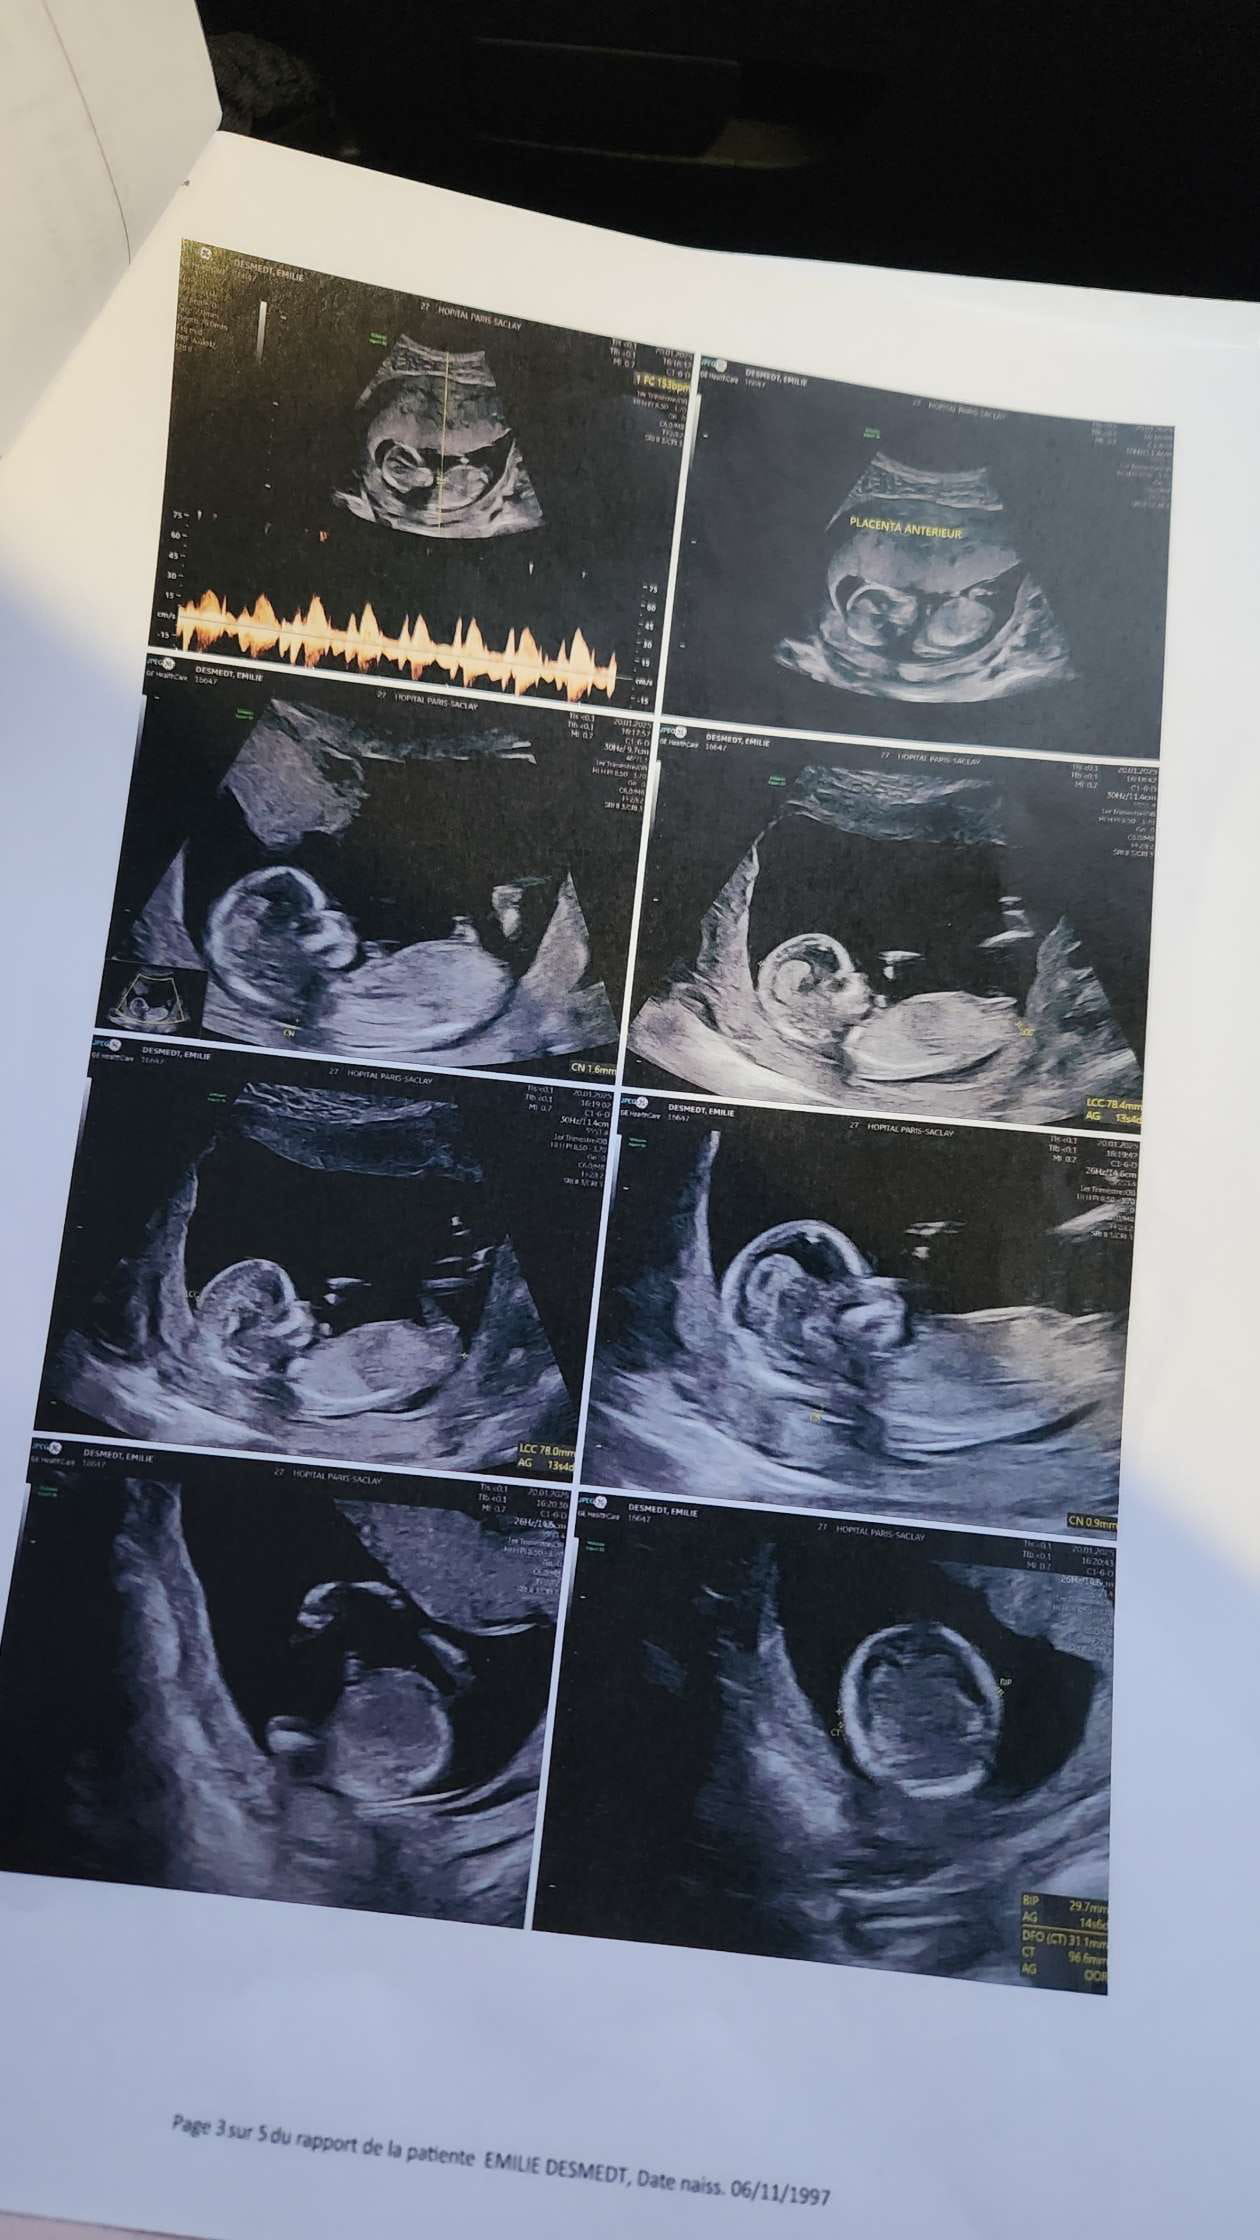

C'est plus prudent de poser cette question directement au médecin qui a procédé à cette échographie.

En France, les médecins le disent dès que ce soit visible et qu'ils en sont sûr ...

Ils demandent par contre, en général, si la femme veut le savoir ou pas car il s'agit d'une liberté de connaître le sexe de l'enfant à naître.